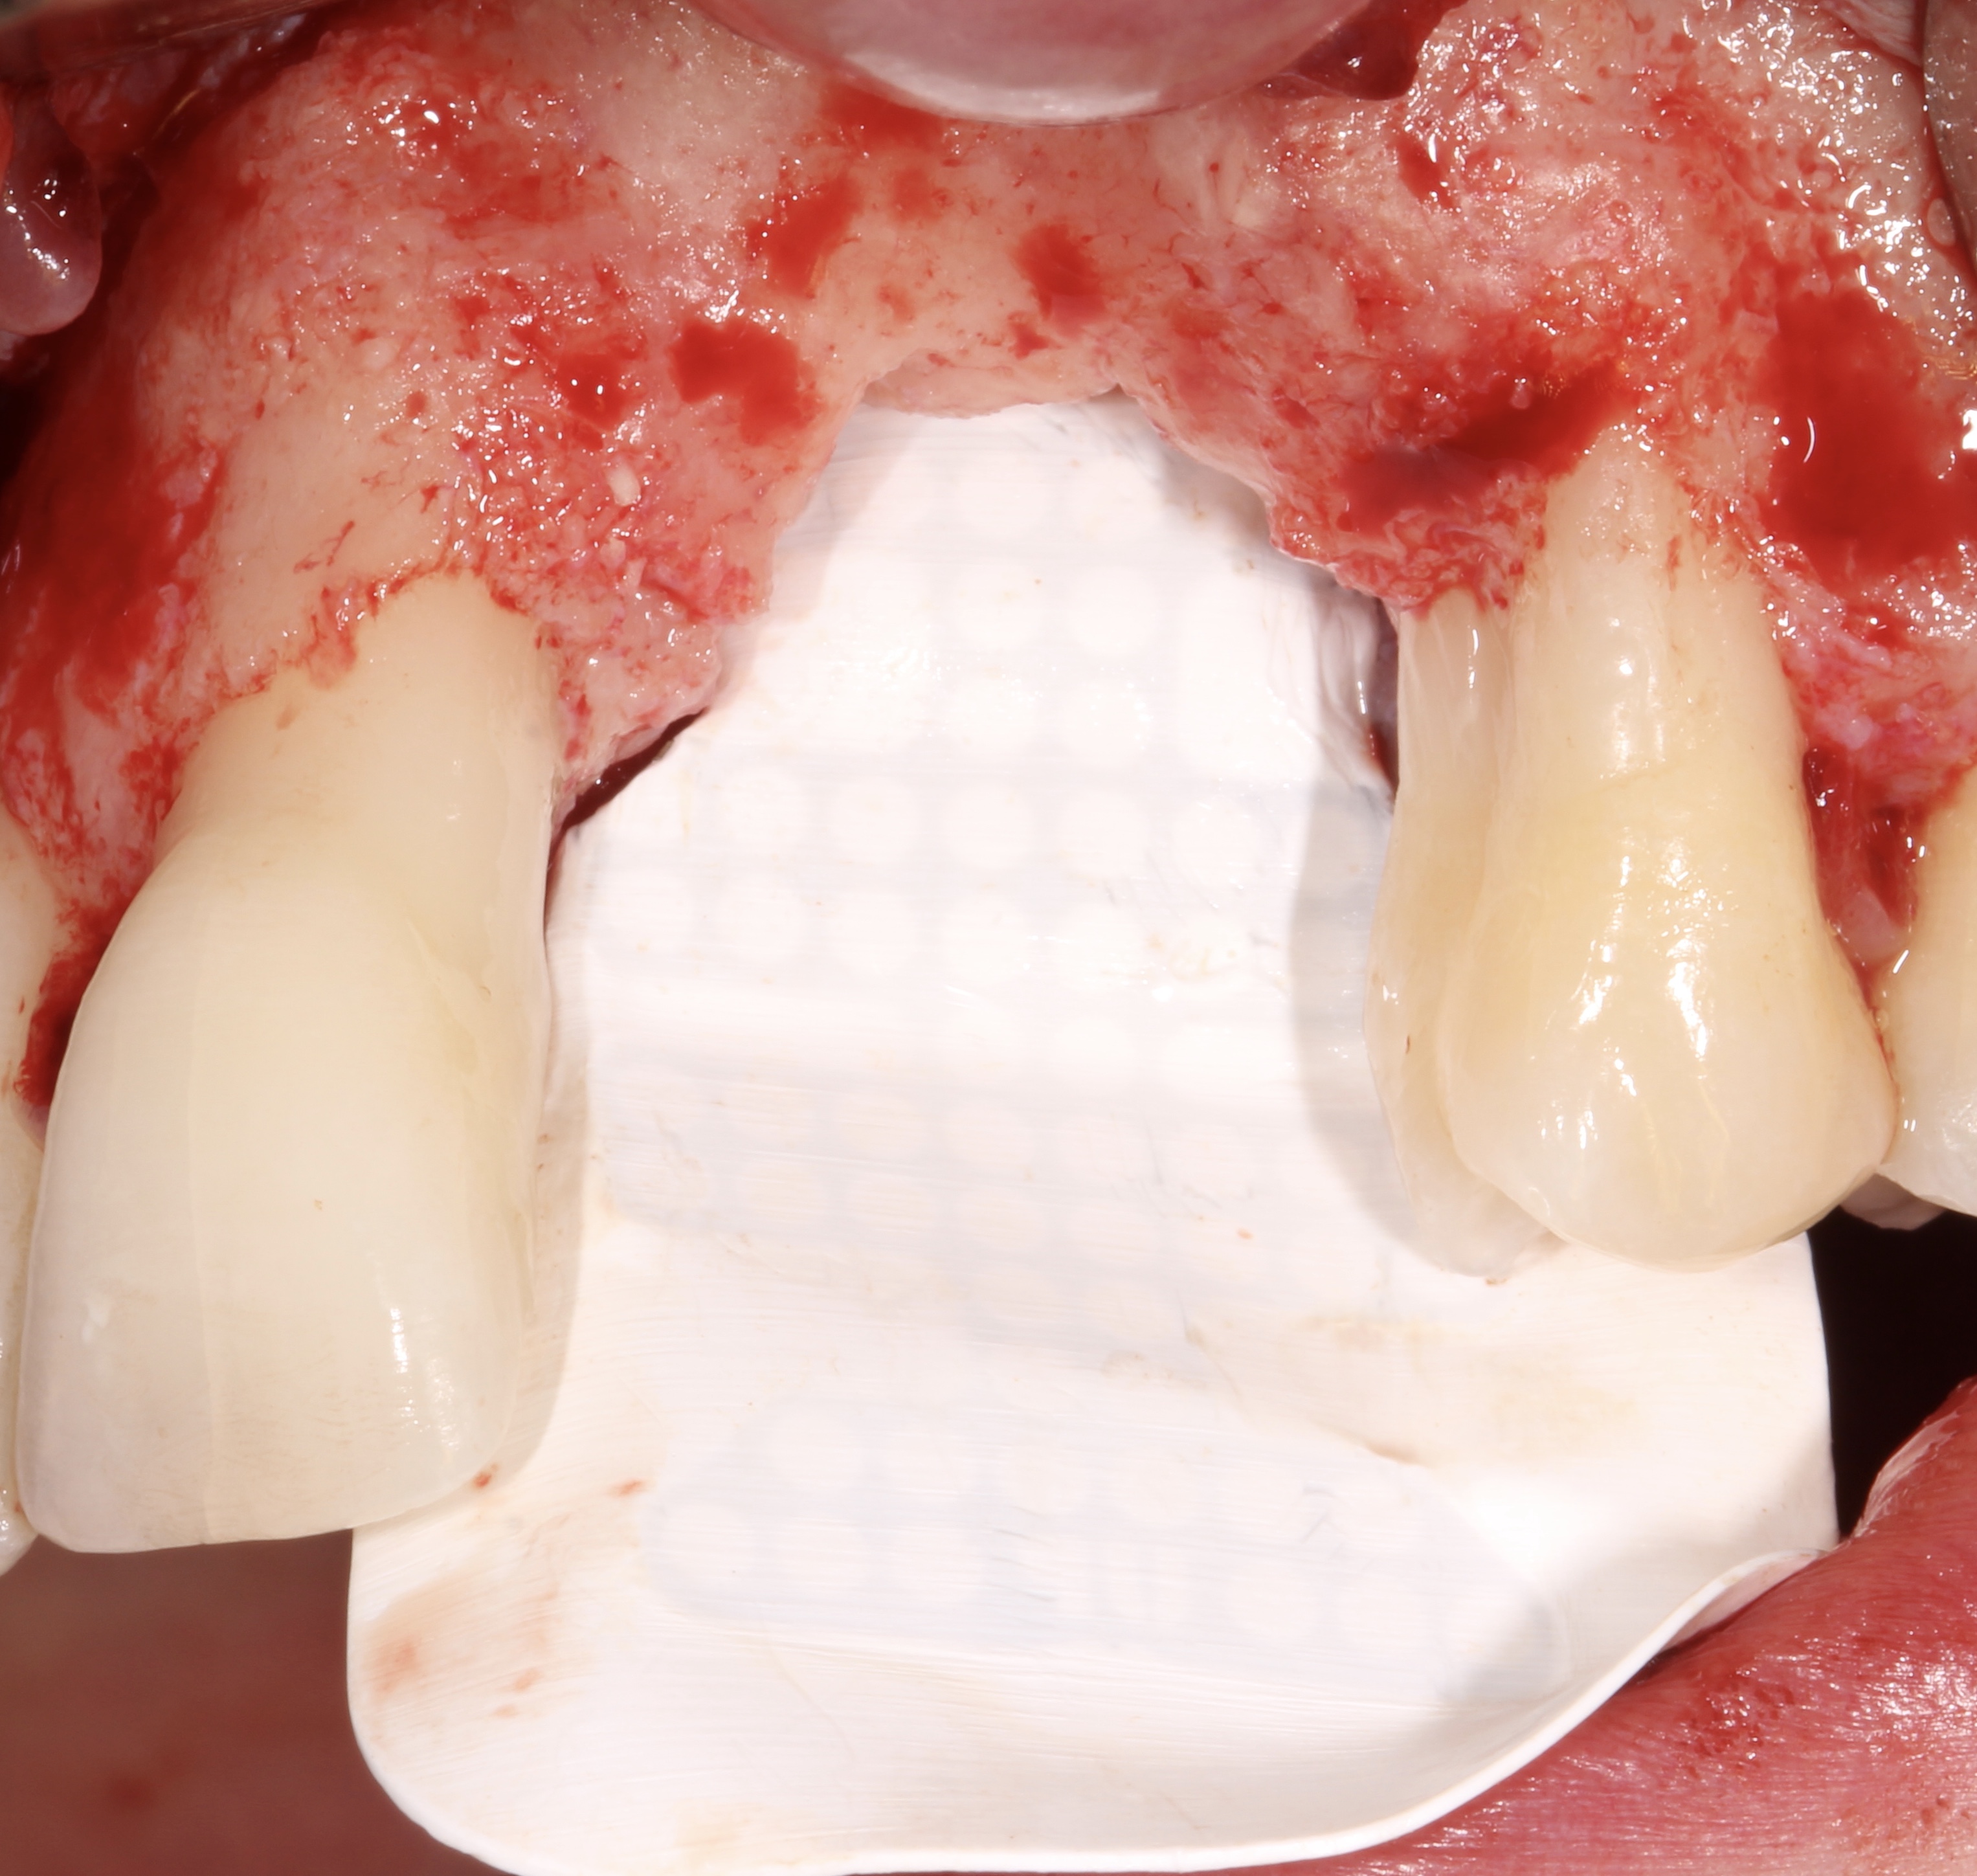

Explantation and Guided Bone Regeneration using a PTFE, Ti-reinforced NeoGen® membrane and 100% autogenous bone.

- 3 months later: (which turned out to be 2 years later because the patients was treated and failed elsewhere): 3D guided bone regeneration using 100% autogenous bone and a PTFE, Ti-reinforced NeoGen® membrane which was fixed by Neoss Tacks.